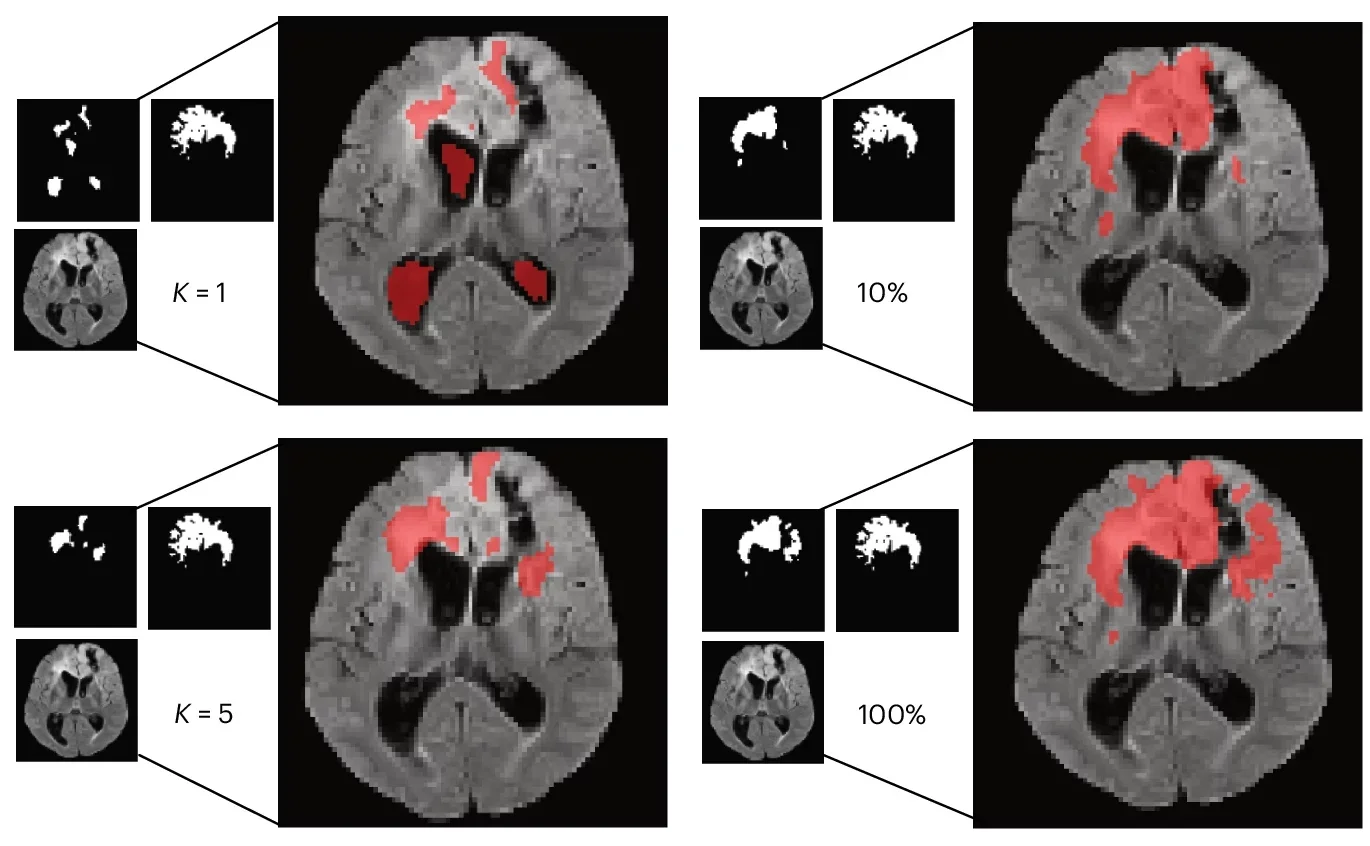

Real clinics do not always have big, labeled datasets waiting for a model. So the team ran few-shot tests. In these trials, the model learned from K = 1 or K = 5 labeled examples per class.

BrainIAC generally held up better than the alternatives. In sequence classification with K = 1, it reached 0.53 balanced accuracy. In IDH mutation prediction with K = 1, it reached an AUC of 0.64. In tumor segmentation, it reached a Dice score of 0.51 with only one sample.